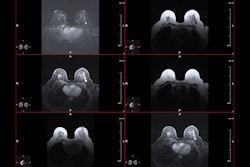

This figure illustrates how AI can extract the full spectrum of predictive information directly from a mammogram, moving beyond the single measure of breast density. While breast density has long been used as a risk factor, it captures only limited information. By contrast, AI analyzes the entire image to provide a personalized five-year risk score, offering a more precise and comprehensive approach to identifying women at increased risk of breast cancer, researchers said.RSNA